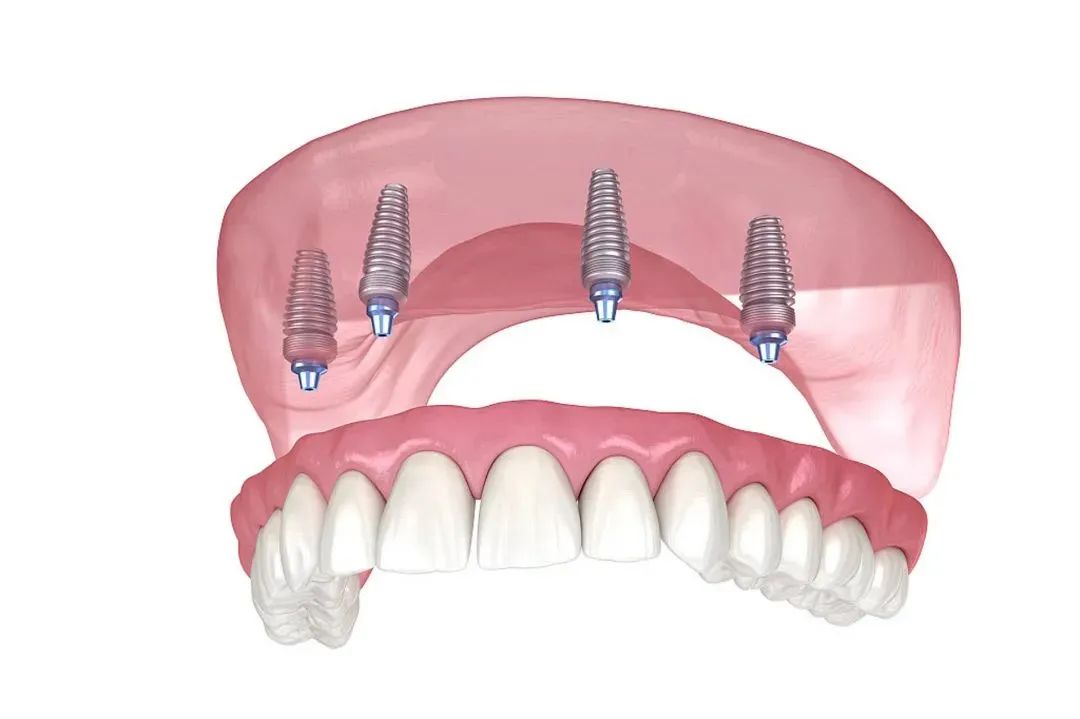

如果你缺了半口或全口牙,數(shù)字化種植的優(yōu)勢(shì)較大。傳統(tǒng)種牙需要種很多顆,手術(shù)時(shí)間長、創(chuàng)傷大。而數(shù)字化種植可以用更少的種植體支撐整排假牙,比如All-on-4技術(shù),只需要種4顆種植體就能支撐半口假牙。